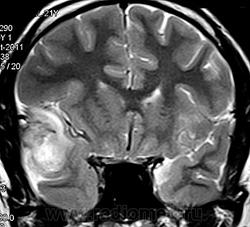

ГМ. Менингосаркома. +

Менингосаркома.